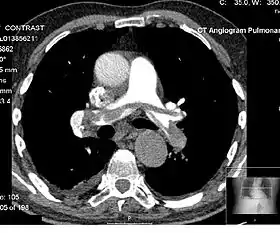

Example of a CTPA, demonstrating a saddle embolus. The white area above the center is the pulmonary artery, opacified by radiocontrast. Inside it, the grey matter is blood clot. The black areas on either side are the lungs, with around it the chest wall. | |

A normal CTPA scan will show the contrast filling the pulmonary vessels, appearing as bright white. Any mass filling defects, such as an embolus, will appear dark in place of the contrast, filling/blocking the space where blood should be flowing into the lungs.

On CTPA, the pulmonary vessels are filled with contrast, and appear white. Any mass filling defects (embolus or other matter such as fat) appears darker. Ideally, the scan should be complete before the contrast reaches the left side of the heart and the aorta, as this may mean contrast has drained from the pulmonary arteries, or require a larger dose of contrast media.[12]